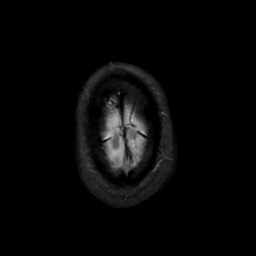

MR Study #4, March 3, 1991 -- Slice #47

[Home][Help][Clinical][Tour 1][Tour 2] Slice 47